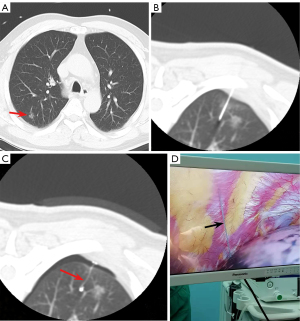

In the conventional coil group, an 18G needle was advanced along the planned needle path into the lung parenchyma. Needle tip placement was verified and adjusted as needed with repeated CT scans. Once the needle tip was positioned within 10 mm of the PN, the coil was inserted through the needle and partially deployed within the parenchyma depending on the depth of PN. Finally, the needle was withdrawn smoothly, and the remaining portion of the coil was left above the pleura (Figure 2).

In novel coil group, a 20 G needle was employed following the same puncture technique as in the conventional coil group. The length of the coil tail was selected according to the depth of PN. When the needle tip was positioned within 10 mm of the PN, a pusher was used to deploy the coil into the lung parenchyma. Finally, the needle was withdrawn smoothly, ensuring the coil tail extended outside the pleura (Figure 3).